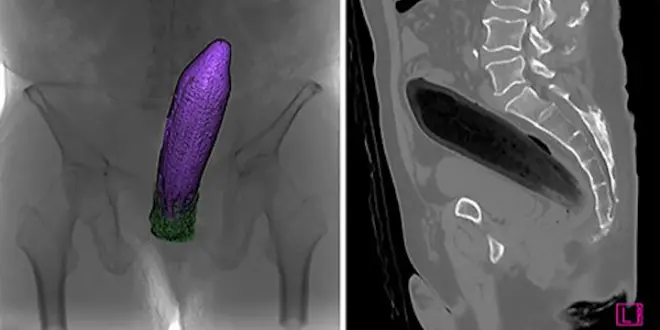

Une dizaine de gastroentérologues se sont relayés pour extraire le légume de manière naturelle.  —  © Faculté de médecine de Hyōgo, Japon.

Ne faites surtout pas ça chez vous ! Au Japon, un homme de 66 ans a consulté pour des douleurs au niveau du rectum. Et pour cause : saoûl, il s'était fait insérer une aubergine de 20 cm dans le rectum par un ami et ne pouvait plus la retirer. Ce cas, documenté en avril dans la revue Case Reports in Gastroenterology, prête à sourire, mais il nécessite une intervention minutieuse. "On essaie d'abord de retirer le corps étranger au doigt pour éviter les risques liés à l'anesthésie. On tente au maximum de limiter les passages au bloc" explique l'urgentiste Anthony Chauvin.

Dans le cas du sexagénaire, une dizaine de spécialistes se sont en effet relayés pour extraire le légume de manière naturelle, sous endoscopie et sans anesthésie. Ils ont pu s’emparer de l'objet grâce à une anse à polypectomie, sans blesser le patient : celui-ci ne présentait pas de signe d’hémorragie ou de perforation intestinale. Aucun acte de chirurgie n’a donc été nécessaire. "Dans 90% des cas, le patient n'a rien. Certains ont même inventé leur propre système pour retirer les objets", précise le Dr Chauvin.